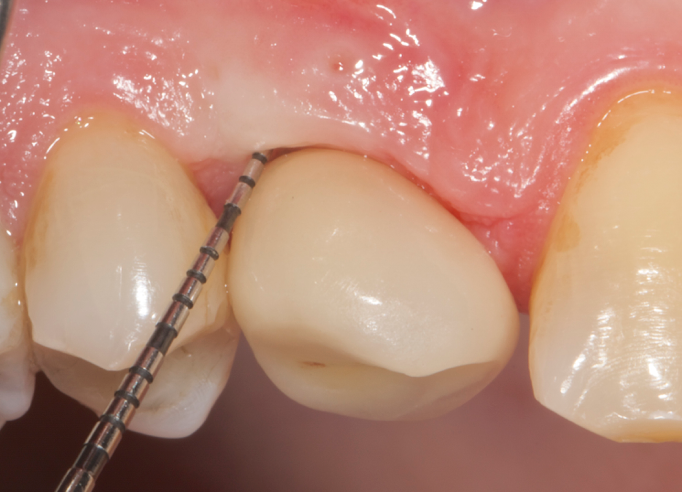

The parameters used to define peri-implant disease usually are: Probing Depth (PD), Crestal Bone Loss (CBL), Bleeding on Probing (BOP) and presence of suppuration and/or fistula.9 Peri-implant mucositis is characterised by soft tissues inflammation witnessed by BOP with or without PD deepening but no effects on the crestal bone while peri-implantitis is characterised by CBL, BOP alone or in conjunction with pus, with or without PD deepening. (Figs. 1, 2 and 3) display the diagnostic steps of a case of peri-implantitis. While mucositis allows a complete healing, peri-implantitis is not reversible.12

Fig.1: Case 1. Peri-implant probing reveals a PPD of 9mm and pus.